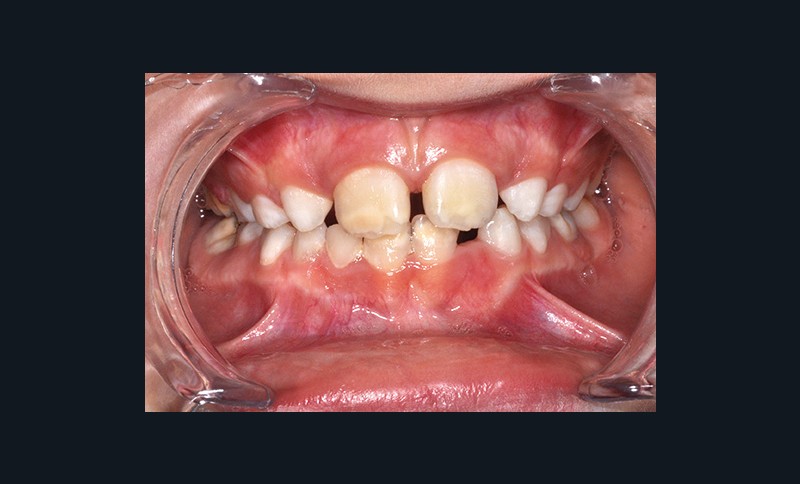

Après l’intervention de Caroline Delfosse, MCU-PH en odontologie pédiatrique à Lille, sur les aspects particuliers de la relation de soin avec l’adolescent, Jean-Pierre Attal, MCU-PH à Paris Descartes, abordera la question très actuelle de l’érosion-infiltration. Cette technique, initialement développée pour stopper le processus carieux dans les secteurs postérieurs, trouve des indications dans la prise en charge des défauts esthétiques antérieurs (white spot, fluorose, dyschromies post-traumatiques). Il présentera également de nouvelles propositions thérapeutiques permettant de traiter les cas de MIH antérieurs qui sont souvent à l’origine de demandes esthétiques fortes (fig. 2).